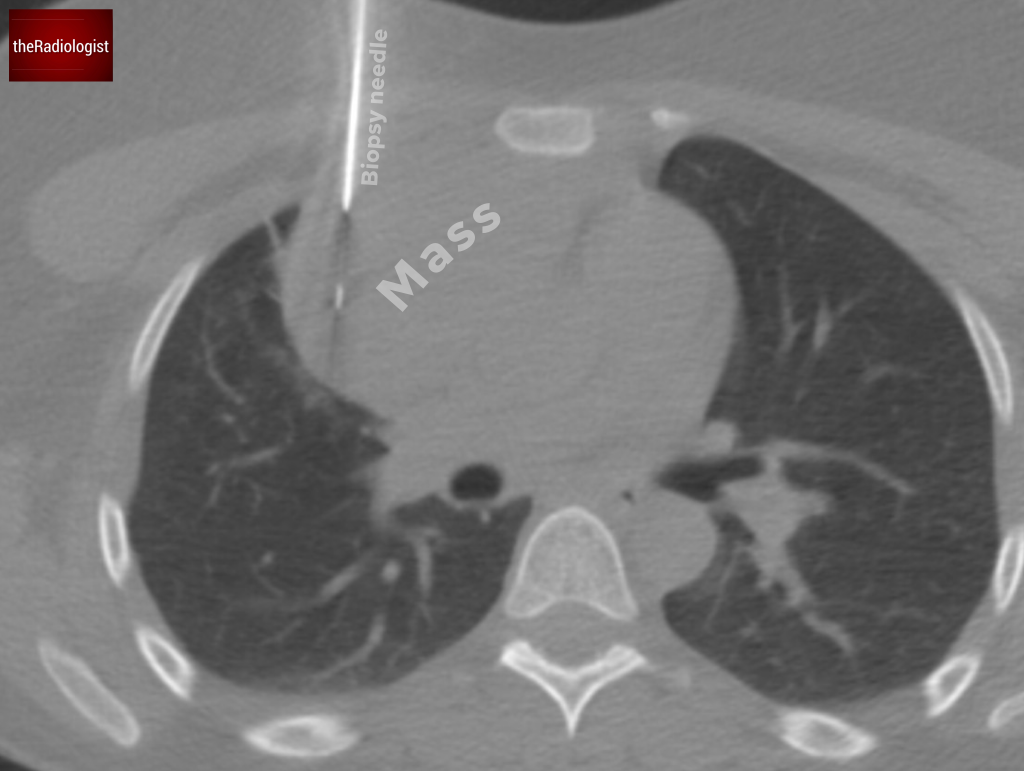

A CT-guided biopsy was performed  through an anterior approach. This confirmed a diagnosis of B-cell lymphoma.

CT guided biopsy of the anterior mediastinal lesion confirmed a diagnosis of B-cell lymphoma.